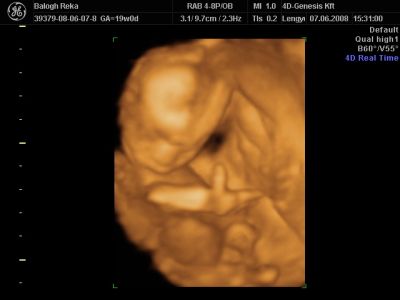

Huhh, hát annyira jó élmény volt, most tök boldog vagyok! Nagyon örülök, hogy mégis elmentem mégegyszer, mert sokat vacilláltam ám. A 4D Genesis egyszerűen szuper, mindenkinek nagyon nagyon tudom ajánlani, ezen belül is engem a Lengyel Györgyné Márti fogadott. Szuper ez a nő, akkora átéléssel és profizmussal csinálta az egész vizsgálatot! Mindent részletesen megnézett, megmutatott, elmagyarázott, nem sajnálta az időt. A felvétel gyönyörű lett, az egész baby nagyon szépen látszik, végig fent volt és mocorgott, hihetetlen aranyos volt, és nagyon szép!

Bemutatott párszor, ezek mind meg is vannak örökítve!

Na és a lényeg...jöjjenek a sztárfotók! Bocsi előre, 8 lesz és kicsit nagyok, de nem tudtam választani, azokat a bemutatásokat mind muszáj volt felraknom, tök vicces!